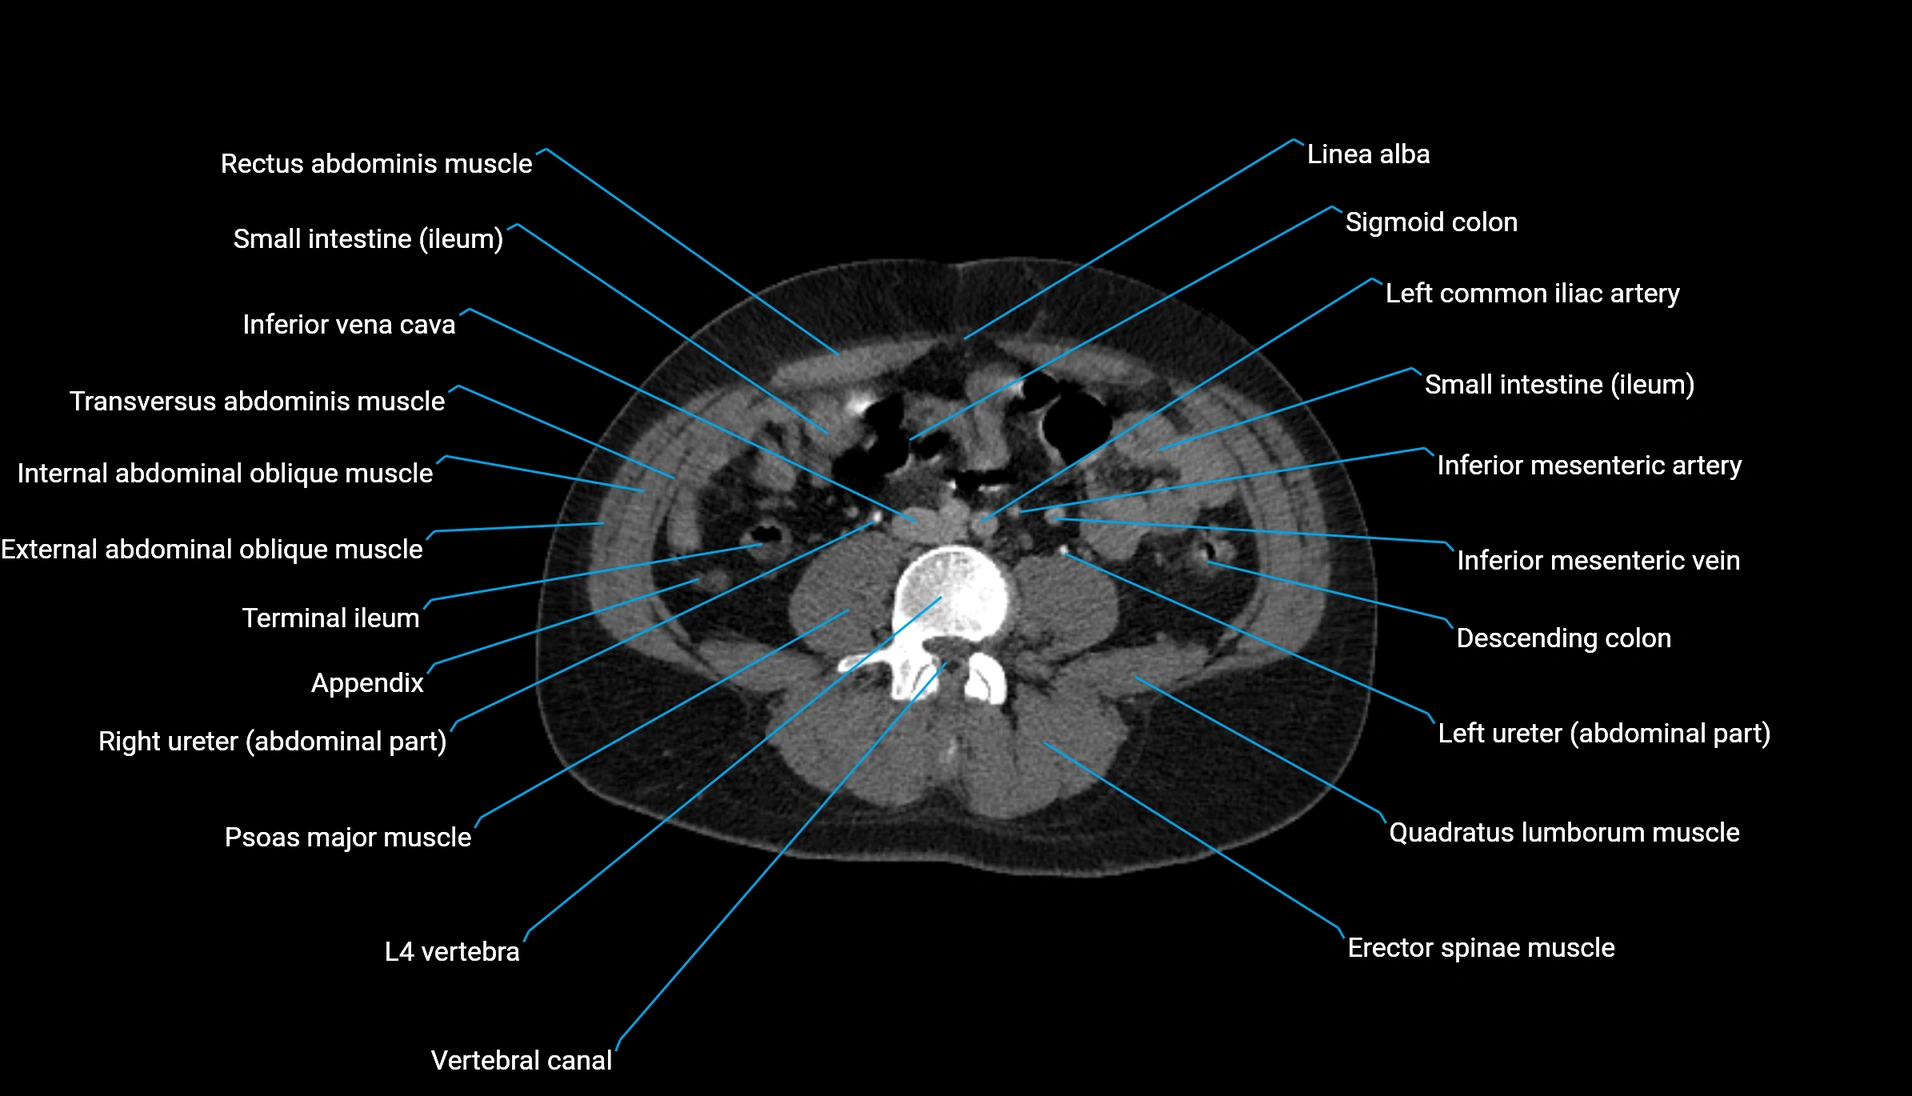

CT Appearance

Non-contrast CT:

-

Demonstrates cortical bone of acetabular rim in excellent detail

Detects fractures, dysplasia, retroversion, or bony overcoverage (pincer impingement)

3D reconstructions used in preoperative hip surgery planning

CT VRT 3D image

CT image